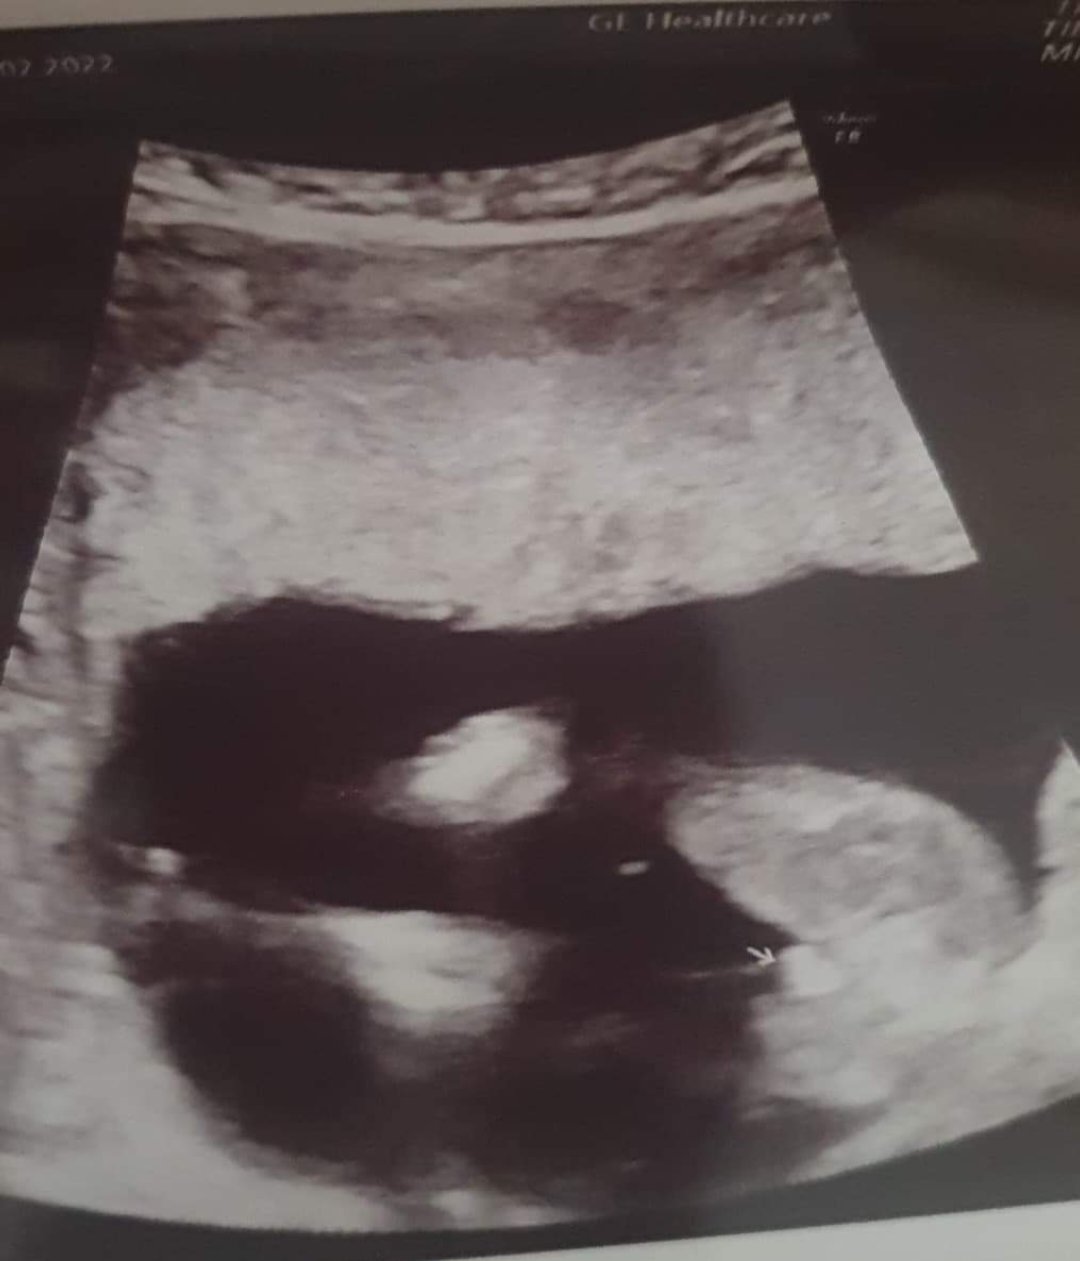

A czy tu napewno kryje sie dziewczynka czy jest szansa ze z buleczki okaze sie ze to sa jajeczka a poprostu siusiaka nie widac? Lekarz w 14 tygodniu stwierdzil synka a 2 tygodnie pozniej 16 tydz na prywatnym usg 3d i u innego lekarza ze dziewczyna

Załączniki

• USER_SCOPED_TEMP_DATA_orca-image-1313013067.jpeg

USER_SCOPED_TEMP_DATA_orca-image-1313013067.jpeg

87,1 KB · Wyświetleń: 189

• USER_SCOPED_TEMP_DATA_orca-image--451202706.jpeg

USER_SCOPED_TEMP_DATA_orca-image--451202706.jpeg

71,9 KB · Wyświetleń: 211

• USER_SCOPED_TEMP_DATA_orca-image-1744876805.jpeg

USER_SCOPED_TEMP_DATA_orca-image-1744876805.jpeg

78,3 KB · Wyświetleń: 195

Bardziej skłaniałbym się przy drugim późniejszym USG, miałam podobna sytuacje. Na prenatalnych 12 tc 80% dziewczynka ( ale wiadomo na te badanie trzeba badać poprawkę) . Zaś moja pani doktór w 14 tc mówiła , że chłopczyk i pokazywała siusiaka, sama go widziałam . Miesiąc później w 18 tc okazało się , że jednak dziewczynka i siusiakiem była pępowina pewnie lub jakoś cień 🤷 w ostateczności wyszła dziewczynka 😅

Ja mam juz core chciałabym miec synka tymbardziej ze to napewno ostatnie dziecko myslicie ze z tej bulki moze sie okazazac jeszcze chlopiec dorosnie tam cos czy sie ukrylo? ludzic sie czy nie to usg bylo prywatne 3d/4d na suoper sprzęcie podobno ja sie nie znam ale cena tez mowila za siebie..